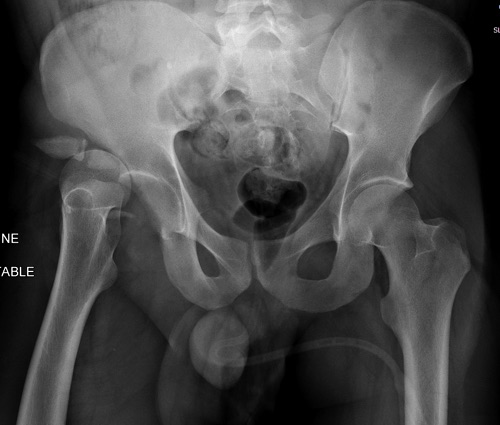

Дискуссия показывает интересные стороны развития тактики лечения переломов вертлужной впадины. Для разработки лечебной тактики сперва надо установить диагноз, и разбор показывает, что не все справляются с такой задачей! Изучение перелома надо начать из стандартных снимков: для переломов костей таза: прямой, inlet и outlet, а для перелома вертлужной впадины - снимки по Judet.

В последнее время, из-за красоты участился показ 3D снимков, хотя надо начать c обычных, и, по необходимости, компьютерная томография с 3D! Без головки бедра 3D покажет общую картину и вовлечение сустава, а более детально только в срезах КТ.

Данная картина показывает очень редкий перелом передней колонны, но перед операцией еще раз надо просмотреть обещанные дополнительные КТ срезы.